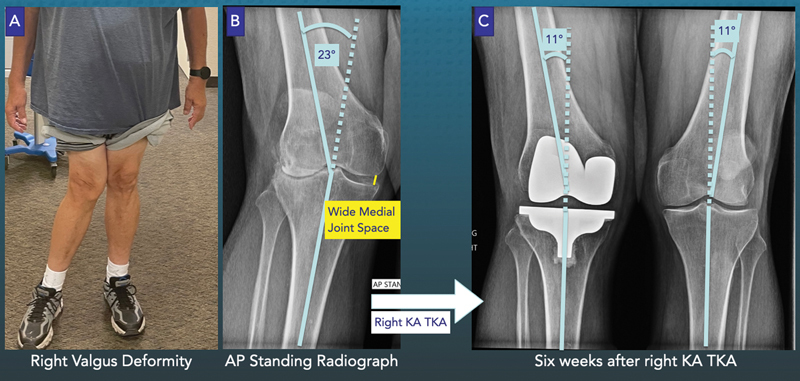

目的:在对伴有外翻畸形的骨关节炎(OA)膝关节进行卡尺验证的运动学配准全膝关节置换术(KA TKA)时,内侧副韧带(MCL)的拉长可能会导致胫骨组件的外翻设置。本研究分析了膝关节外翻畸形患者的 KA TKA(即、2)外侧副韧带(LCL)和后交叉韧带(PCL)松解的发生率以及受限组件的使用情况、3)对于髋关节外翻≤10°的OA畸形,一年的 "遗忘关节评分"(FJS)、"牛津膝关节评分"(OKS)、"膝关节损伤和骨关节炎关节置换术结果评分"(KOOS JR)和Likert满意度评分是否与KA TKAs相当。方法:对由一名外科医生实施 KA TKA 的 112 名连续患者进行了至少 1 年的放射学和临床随访分析。胫骨组件相对于OA胫骨关节线的外翻方向大于1°,即可确定MCL的影像学伸长:26名患者的胫股关节放射解剖角度大于10°外翻(OA畸形范围为11°至23°外翻)。76名患者的OA畸形≤10°外翻(10°外翻至-14°内翻)。没有患者出现 MCL 拉长、韧带松解或需要约束组件。OA外翻畸形大于10°的患者的FJS中位数为78,OKS中位数为42,KOOS JR中位数为76,满意率为85%,与OA外翻畸形小于10°的患者相比无显著差异(P≥0.17):由于在外翻23°以下的OA畸形中未检测到MCL伸长,因此在不释放LCL和/或PCL的情况下使用主组件进行KA TKA手术时,外翻畸形矫正不足导致不稳定和不良结果评分的风险很低。

When performing caliper-verified kinematically aligned total knee arthroplasty (KA TKA) in the osteoarthritic (OA) knee with valgus deformity, an elongated medial collateral ligament (MCL) could result in a valgus setting of the tibial component. The present study analyzed KA TKA in patients with valgus deformities (i.e., tibiofemoral angle > 10 degrees of valgus) and determined (1) the occurrence of radiographic MCL elongation, (2) the incidence of lateral collateral ligament (LCL) and posterior cruciate ligament (PCL) release and the use of constrained components, and (3) whether the 1-year Forgotten Joint Score (FJS), Oxford Knee Score (OKS), Knee Injury and Osteoarthritis Outcome Score for Joint Replacement (KOOS JR), and Likert satisfaction score were comparable to KA TKAs for OA deformities ≤10 degrees of valgus. One hundred and two consecutive patients who underwent KA TKA by a single surgeon were analyzed radiographically and clinically at a minimum follow-up of 1 year. Radiographic MCL elongation was identified by a greater than 1 degree of valgus orientation of the tibial component relative to the OA tibial joint line. Twenty-six patients had a radiographic anatomic tibiofemoral angle greater than 10 degrees of valgus (range of OA deformity: 11-23 degrees of valgus). Seventy-six had an OA deformity ≤10 degrees of valgus (10-degree valgus to -14-degree varus). No patient had MCL elongation or a ligament release, or required constrained components. The median FJS of 78, OKS of 42, and KOOS JR of 76, and the 85% satisfaction rate of the patients with greater than 10 degrees of OA valgus deformity were not significantly different from those with ≤10 degrees of OA valgus deformity (p ≥ 0.17). Because MCL elongation was not detected in OA deformities up to 23 degrees of valgus, the risk of under-correcting the valgus deformity leading to instability and poor outcome scores is low when performing KA TKA using primary components without releasing the LCL and/or PCL. LEVEL OF EVIDENCE::  IV.